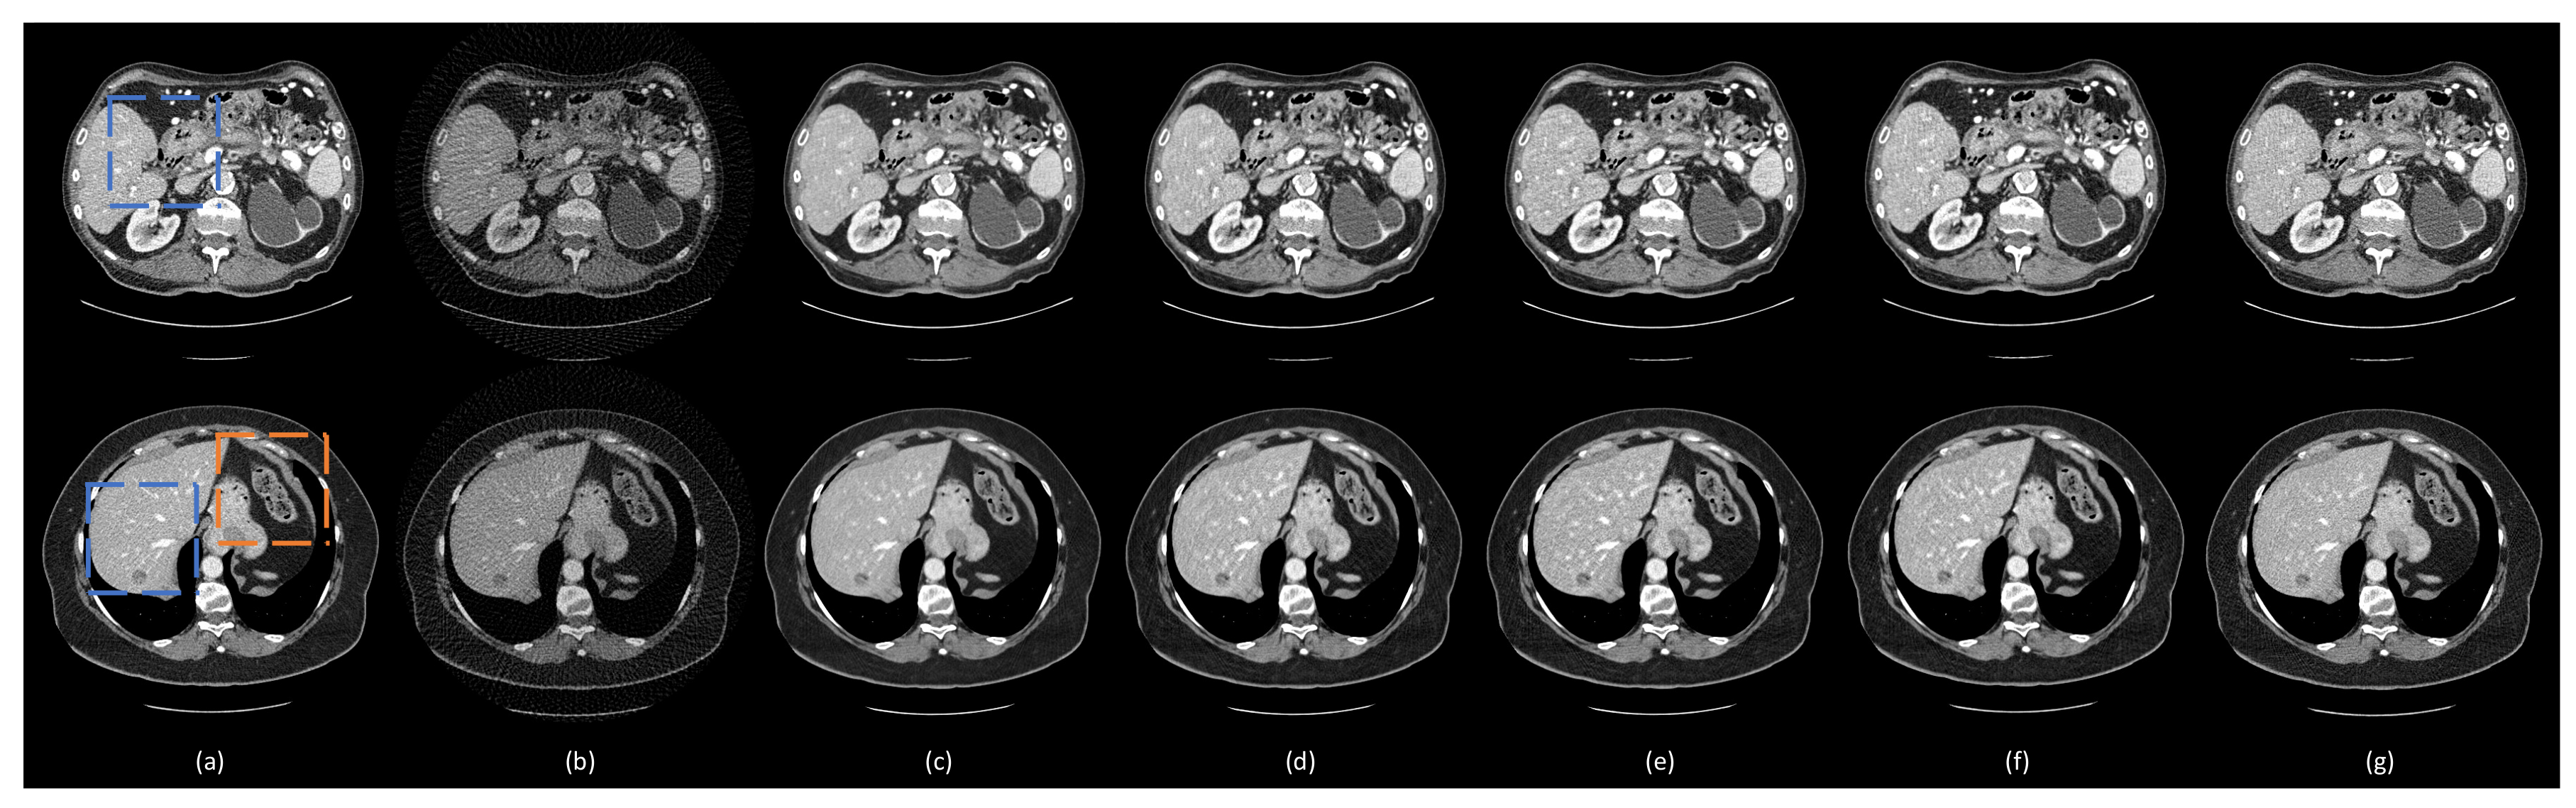

- (1)

3.3. Comparison with Other Deep Learning Methods